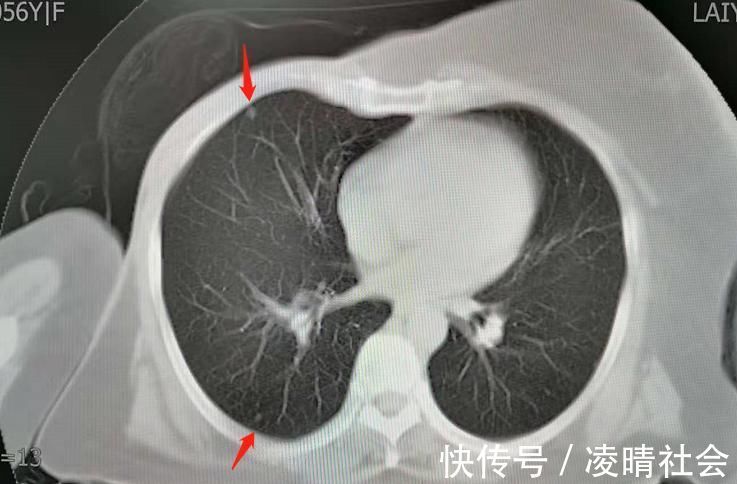

这是一位乳腺癌手术后的病人,发现双肺多发小结节,考虑转移,很要强的一位病人,听从医生指导做过化疗,平时喜欢旅游,对吃的东西也很上心,偶尔还去跳广场舞。用她的话说,活着就要开心点!多赚一年是一年!

今年已经第8年了,病灶虽然有进展,总体很稳定,56岁发现转移,现在已经64岁了,很坚强的8年抗战: